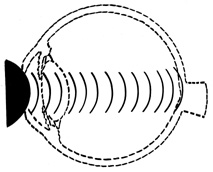

COUP AND CONTRECOUP

Courville24,25 introduced the concept of coup and contrecoup injury to explain brain damage caused by blunt trauma to the head. Coup refers to local trauma at the site of impact. Contrecoup refers to injuries at the opposite side of the skull caused by shock waves that traverse the brain. Foci of brain damage are found along the path of the shock waves, especially at interfaces of tissues of different density. The greatest difference in density is between the brain and the skull, and it is here that the most severe damage occurs. Wolter later used these concepts to explain eye injuries.26 Examples of coup injuries are corneal abrasions, subconjunctival hemorrhages, choroidal hemorrhages, and retinal necrosis (Fig. 1). The best example of a contrecoup injury is commotio retinae (Fig. 2). These injuries are discussed later in this chapter.

Fig. 2. Contrecoup injury. When a blunt object strikes the eye, shock waves traverse the eye to strike the posterior pole.